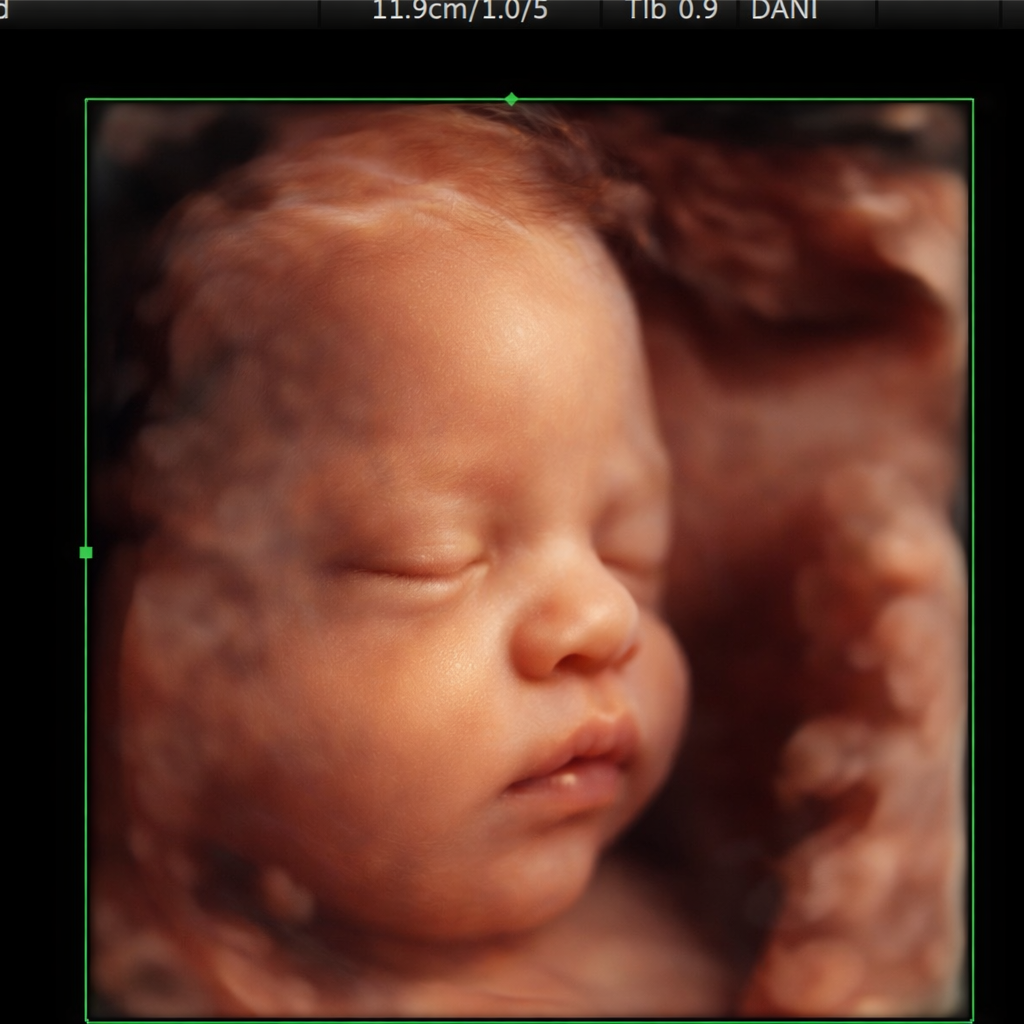

First Trimester

6 -13 Weeks - 15-25 Min Scan Listen to Baby’s Heartbeat and see your baby in 2D. Includes 5 + black and white printed photos- If we see gender we can confirm. See your little sweetie for the first time. Waiver must be completed before we can scan you. Come with a full bladder :)